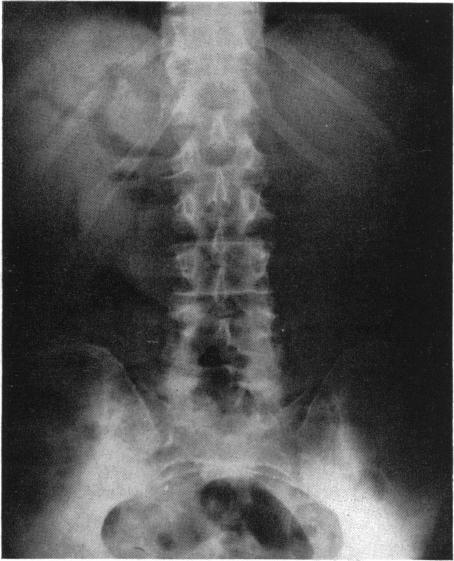

CARCINOMA OF THE PANCREAS AND AMPULLARY REGION: REPORT OF SIX ADDITIONAL CASES.

Ann Surg. 1942 Jun;115(6):1066-90. doi: 10.1097/00000658-194206000-00018.